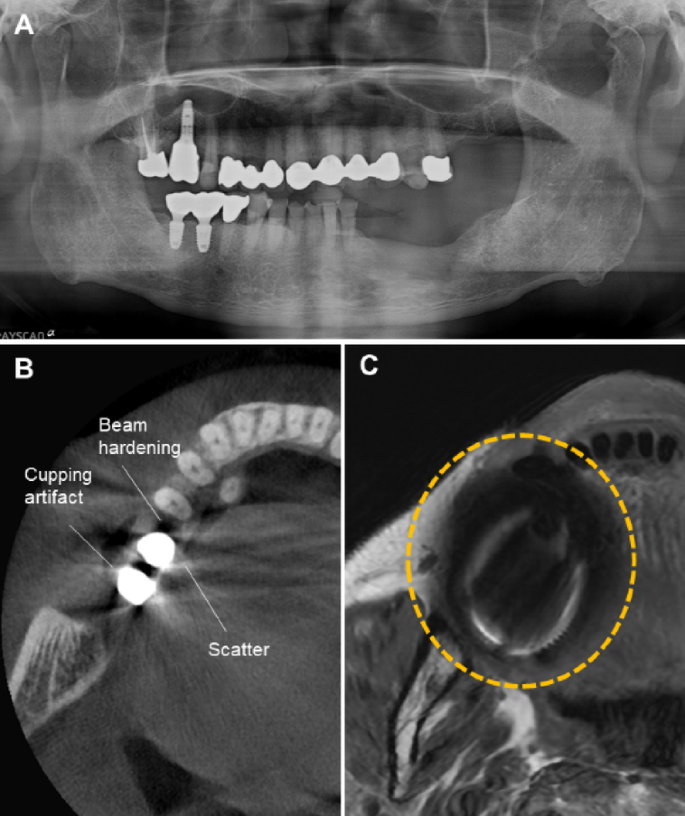

As the population ages, the prevalence of intraoral prostheses—including dental implants—continues to rise. Various prosthetic materials produce metal artifacts due to differences in magnetic susceptibility between the prosthetic material and the surrounding tissues.3,4 Magnetic susceptibility refers to the property of a material to become magnetized when exposed to a magnetic field. While human tissues exhibit weak diamagnetic properties, metals typically have paramagnetic or ferromagnetic characteristics.3,4 When metal is placed within the main magnetic field of MRI, it generates an additional magnetic field in its vicinity, making the main field inhomogeneous and leading to the occurrence of metal artifacts. Metal artifacts are defined as signal intensity distortions and signal loss surrounding a prosthesis and differ in appearance from the metal artifacts observed in computed tomography (CT) or cone-beam computed tomography (CBCT) (Fig. 1).1 These artifacts hinder the accurate assessment of lesion signal intensity and, in severe cases, obscure critical anatomical regions, making diagnosis difficult (Fig. 2). Previous studies have investigated MRI artifacts associated with various types of metallic dental prostheses and materials.5,6 Metal crowns and orthodontic stainless steel wires have been shown to produce more pronounced artifacts, while zirconia and resin materials are associated with less severe artifacts.

A patient with multiple dental prostheses and implants. (A) Panoramic radiograph. (B) Axial CBCT image showing metal artifacts: cupping artifacts (distortion of metallic structure), beam hardening (dark bands), and scatter (white streaks). (C) Axial MR image. Metal artifacts (dashed circle) appear as a dark and bright area adjacent to the prosthesis.